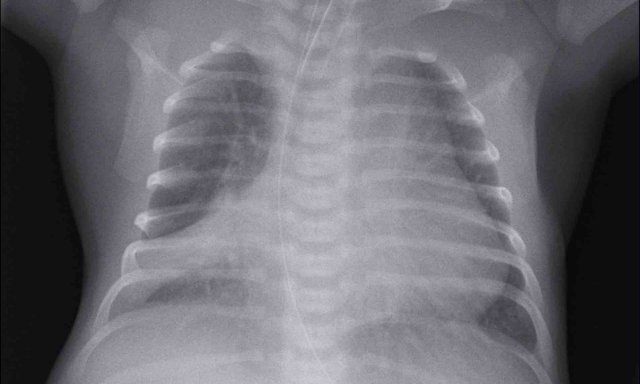

Image

One day old neonate, 27 weeks of gestational age.

Granular opacification of both lungs.

Vessels and cardiac silhouette are well depicted.

Conclusion: RDS grade 1.

Peripherally inserted central catheter (PICC) line, curled in the right atrium.  The PICC should be pulled back to the level of the superior vena cava and right atrium.